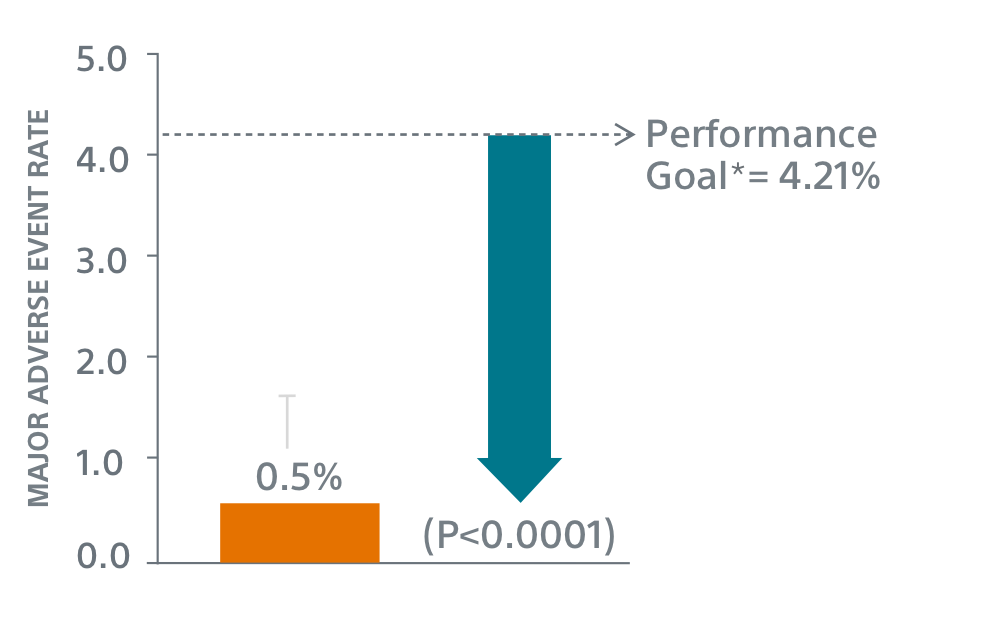

PINNACLE FLX

Study Design

- 400 patient, 29 US site, single arm, non-randomized trial evaluating WATCHMAN FLX for non-inferiority to safety and efficacy performance goals based on the WATCHMAN™ device.

- Follow-up: 45 days (+TEE), 6 months, 12 months (+TEE), 18 months, and 24 months

- Patient Characteristics: Average CHA2DS2-VASc of 4.2±1.5, Average HAS-BLED of 2.0±1.0

- Post Implant Drug Regimen: NOAC/ASA for 45 days, Clopidogrel/ASA to 6 months, ASA post 6 months

- Primary Safety Endpoint: All-cause death, ischemic stroke, systemic embolism, or device- or procedure-related adverse events requiring surgery or major endovascular intervention within 7 days following the procedure or by hospital discharge, whichever is later.

- Primary Efficacy Endpoint: The rate of effective LAA closure defined as any peri-device flow ≤5mm demonstrated by TEE at 12 months

- Secondary Efficacy Endpoint: The occurrence of ischemic stroke or systemic embolism at 24 months from the time of enrollment

- Inclusion/exclusion criteria is consistent with WATCHMAN clinical study inclusion/exclusion criteria. Patients must be eligible for short-term NOAC vs warfarin in previous clinical studies.

Primary Safety Endpoints

Primary Efficacy Endpoints

The rate of effective LAA closure defined as any peri-device flow ≤5mm demonstrated by TEE at 12 months.

** Performance goal pased on the rates observed in PREVAIL(1) and CAP2(2), minus a clinically relevant delta